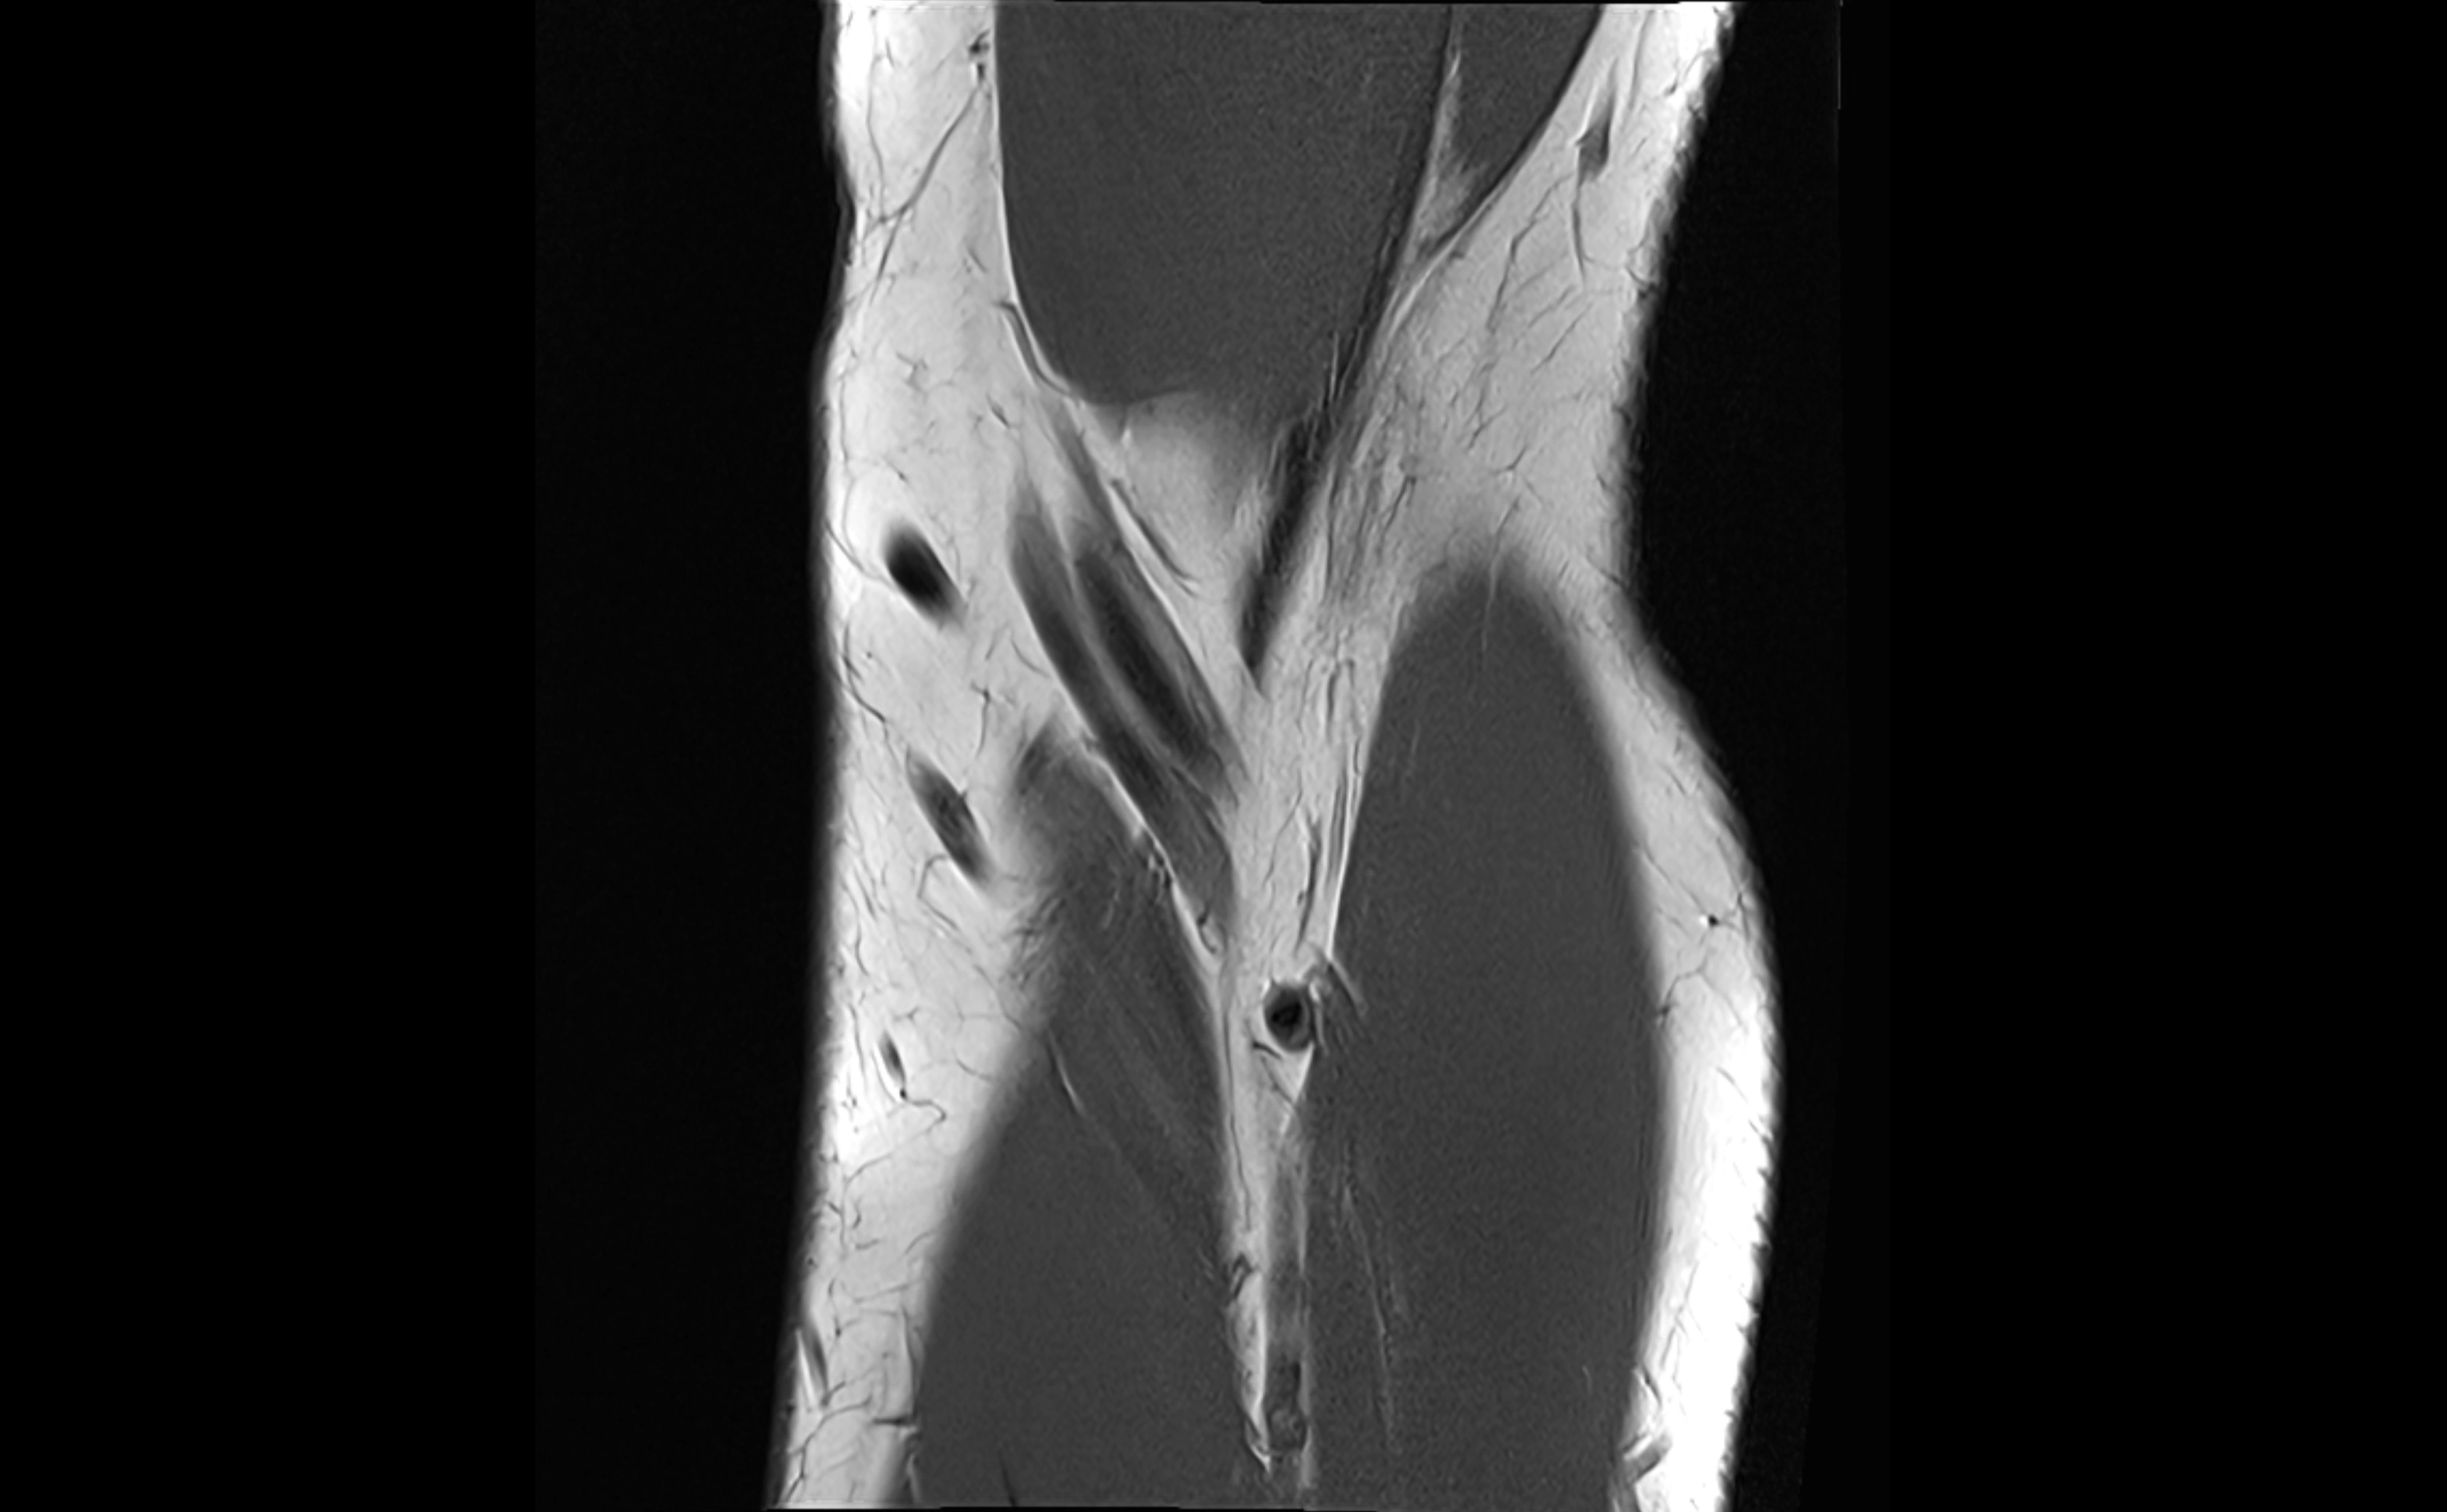

MRI images

image